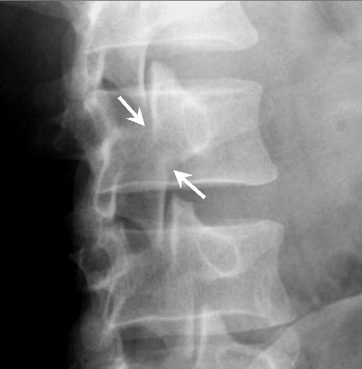

diagnosis?

collar on scotty dog appearance = Spondylolysis

Spondylolysis = fracture of pars interarticularis (sticking out bit of vertebra)

Spondylolisthesis: fracture + slipping of one vertebral body on another